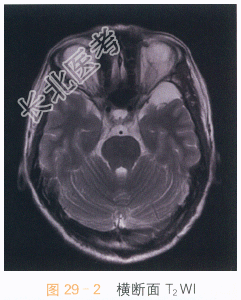

影像学资料如图29-1~图29-4所示。

读片分析:头颅横断面T₁WI、T₂WI见左侧中颅窝异常信号灶,呈长T₁WI、长T₂WI信号,边界清晰,左侧颞极受压,信号无明显异常改变;冠状面T₂WI及矢状面T₁WI亦可见左侧中颅窝长T₁WI、长T₂WI信号影,左侧颞极受压改变。结合患者病史,诊断为蛛网膜囊肿。